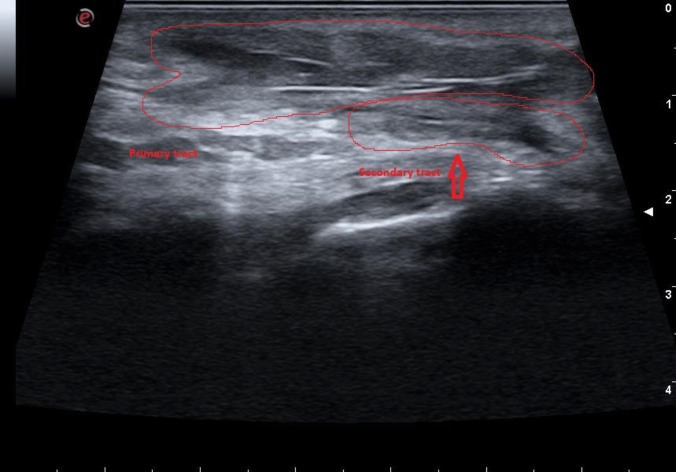

Background: Pilonidal disease (PD) is frequently associated with high recurrence rates and delayed healing, particularly in complex or recurrent cases. While Endoscopic Pilonidal Sinus Treatment (EPSiT) has improved postoperative recovery and patient satisfaction, its effectiveness can be limited by incomplete identification of fistulous tracts. Intraoperative ultrasound (IUS) offers real-time visualization of subcutaneous structures and may aid in detecting hidden tracts during surgery. This study evaluates the clinical outcomes of combining IUS with EPSiT in the treatment of complex and recurrent PD.

Materials and methods: A retrospective cohort, single-center study was conducted on patients with recurrent and complex PD treated between 2018 and 2021 using IUS in conjunction with EPSiT. All patients had a minimum follow-up of 36 months. The study recorded the number of cases in which IUS identified additional fistulous tracts and led to a modification of the surgical strategy, as well as clinical outcomes including recurrence rate, time to wound healing, and incidence of incomplete wound healing.

Results: Nineteen patients were included (14 males, 73.7%; mean age of 35.4 ± 6.4 years). The mean operative time was 42 min, with IUS requiring an additional 6 min. IUS identified previously undetected fistulous tracts in 6 patients (31.5%), leading to modifications in the surgical strategy. At 36-month follow-up, disease persistence (recurrence or incomplete healing) was observed in 5 patients (26.3%). Recurrent cases were successfully managed with additional procedures, achieving 100% healing after reintervention.

Conclusions: Intraoperative IUS identified previously undetected secondary tracts in 31.5% of patients, leading to a modification of the surgical approach. Further comparative studies are needed to validate its effectiveness and assess its potential role as a standard adjunct in the surgical management of pilonidal disease.